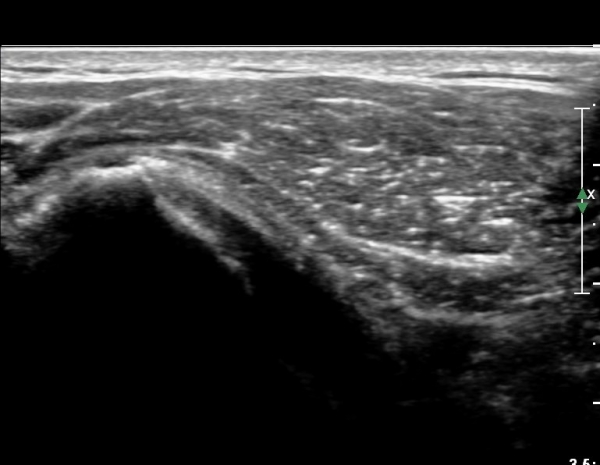

¼®È¸ À§ÂÊ(¸Ó¸®ÂÊ)ÀÇ ÈûÁÙÀÇ Àú¿¡ÄÚ º¯È­°¡ °üÂûµÈ´Ù(»çÁø 4, 5).

Á¡¾×³¶³» ÁÖ»ç ÈÄ ÁÖ»ç¹Ù´ÃÀ» ¹Ýº¹ÀûÀ¸·Î ´õ ÁøÀÔ½ÃÄÑ ¼®È¸¸¦ ÀÚ±ØÇÏ´Â ¸ð½À(»çÁø 5, 6)